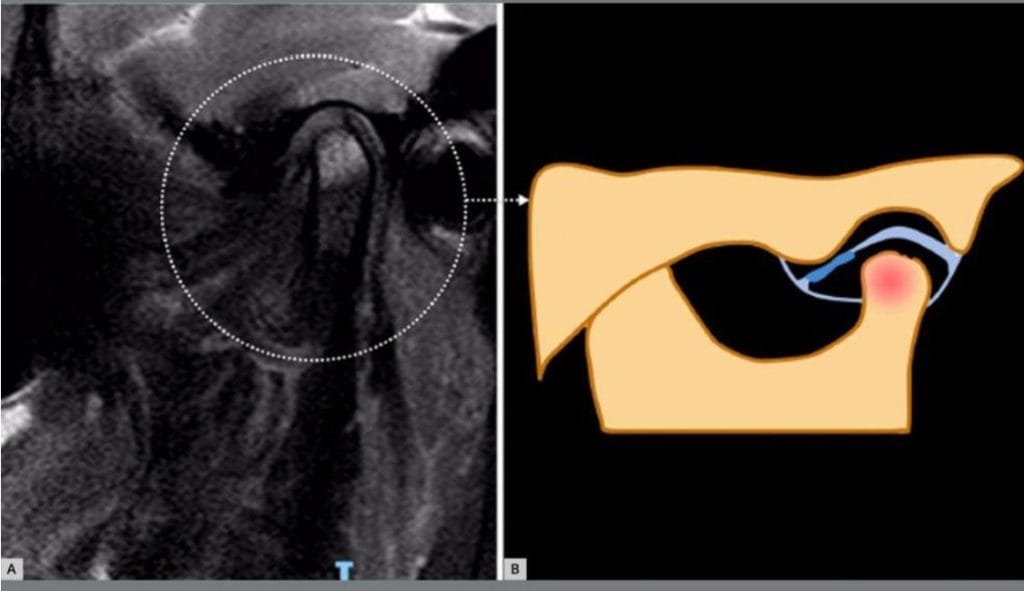

Foram identificados cinco fenótipos estruturais distintos por ressonância

magnética:

1. Adaptativo

2. Erosivo

3. Hipertrófico

4. Inflamatório

5. Ósseo

● Cada fenótipo demonstrou características específicas de sinal e alterações

estruturais nas imagens.

● Essa classificação pode melhorar a interpretação clínica da ressonância

magnética, além de orientar a seleção de intervenções terapêuticas mais

adequadas.